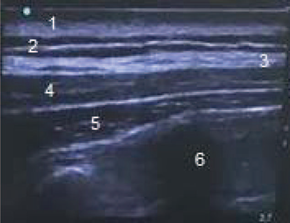

Dos días después, la paciente es traslada a quirófano para realizar mastectomía derecha más vaciamiento ganglionar axilar. Se realiza monitoreo básico con cardiovisoscopio de 3 canales, toma de tensión arterial no invasiva, medición de saturación y control de hipotermia con manta térmica. Como monitoreo neurológico usamos el BIS (Índice biespectral). Se realiza inducción anestésica endovenosa con Fentanilo 200 mcgr, Propofol 120 mg, Rocuronio 36 mg, dando mantenimiento con anestesia general balanceada con Sevoflurane Concentración alveolar mínima (CAM) 0.6-0.7, Remifentanilo 0.15 - 0.2 mcgr/ Kgr/min, parámetros dinámicos para mantener BIS 40-45. El grupo de Ginecooncología realiza mastectomía simple derecha más vaciamiento ganglionar axilar y resección de fascia pectoral mayor, obteniendo una pieza quirúrgica correspondiente a mama derecha con un peso de 5020 gr. Durante el procedimiento se administra: Dexametasona 8 mg IV para prevención de náuseas y vómito, Dipirona 2,5 gr y Diclofenaco 75 mg IV. Al terminar el procedimiento quirúrgico, bajo anestesia general, el equipo de anestesiología a cargo del caso, procede a realizar bloqueo del elevador de la espina. Se posiciona la paciente en de cubito lateral izquierdo, previa asepsia y antisepsia, se realiza sonoatomia a nivel T6-T7 y paravertebral derecho, con transductor ecográfico lineal de alta frecuencia, identificando de afuera hacia adentro: 1. Piel, 2. tejido celular subcutáneo, 3. musculo Trapecio, 4. musculo Romboides mayor, 5. musculo elevador de la espina, 6. apófisis transversa (Fig. 2), con aguja N° 50 mm ecosensible, con un abordaje en plano en sentido cefalocaudal hasta llegar al musculo elevador de la espina, se administró Bupivacaína con Epinefrina al 0.25% y Lidocaína al 0.5% (volumen total 20 mL) logrando hidrodisección satisfactoria del musculo elevador de la espina. La paciente adicionalmente tuvo una analgesia controlada por el paciente (PCA) de morfina endovenosa como propuesta analgésica de rescate. Se valoró a las 4 horas encontrándose un área de anestesia comprendida por hemitórax anterior derecho y zona axilar, en región posterior anestesia desde T4 a T12. Se realizó seguimiento del dolor a través de la escala visual análoga (EVA) durante 30 horas. (Tabla 1)